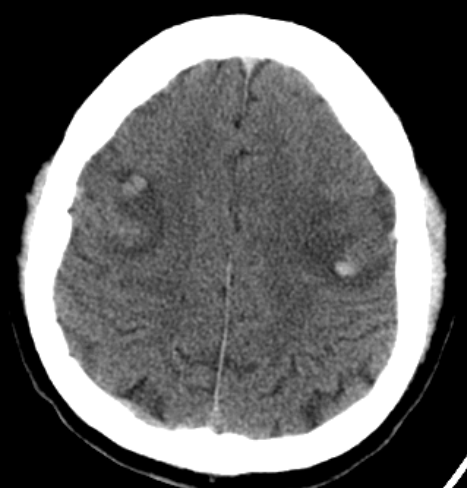

La angiotomografía cerebral evidencia la presencia de múltiples áreas hiperdensas de distribución difusa, bilateral que compromete ambos lóbulos frontales, compatibles con hemorragias intraparenquimatosas de focos múltiples, asociado a edema perilesional (Fig 1 y 2), además se identificó la presencia de signo del delta vacío secundario a trombosis venosa dural que compromete el seno sagital superior, con extensión a la confluencia de los senos, seno transverso derecho, así como el seno yugular y vena yugular ipsilateral (Fig 3 y 4).

FIGURA 1,2. Imágenes de angiotomografía cerebral en proyección axial y sagital, en ventana de cerebro que muestra la presencia de múltiples áreas hiperdensas en lóbulos frontales, de distribución difusa, bilateral.